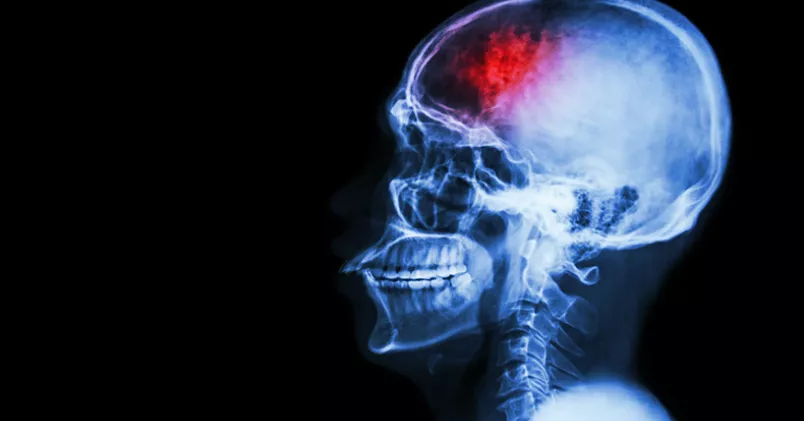

Stroke mer dödligt för låginkomsttagare

Personer med låg inkomst har sämre chans att överleva efter en stroke. Det visar en ny avhandling från Umeå Universitet.

Risken att dö efter en stroke ökar om du har låg lön. Puwadol Jaturawutthichai / Colourbox

Ett år efter att ha drabbats av stroke har låginkomsttagare närmare fem procents sämre chans att överleva än höginkomsttagare. Statistikern Anita Lindmark har i sin färska doktorsavhandling mätt överlevnaden efter stroke efter en vecka, en månad respektive ett år.

– Redan den första månaden så dök det upp skillnader. Sedan blev siffran högre, säger Anita Lindmark.

Hennes forskning baseras på uppgifter från registret Riksstroke och bygger på 62 000 personer som mellan 2001 och 2009 drabbades av stroke för första gången. Den minskade överlevnaden på grund av låg inkomst är jämförbar med den effekt som rökning har.

– Det finns forskning om andra sjukdomar med liknande resultat. Men det är viktigt att belysa sådana här skillnader. Bland annat för att kunna ge mer riktade insatser, både förebyggande samt under och efter stroken, för de grupper som tycks vara mer utsatta.

Enligt Anita Lindmark finns det olika förklaringar till detta, både på individ- och på strukturnivå. Kvinnor har till exempel bättre överlevnad, troligen för att de söker vård tidigare än män. Andra studier på Riksstroke visar att patienter med låg utbildning får sämre tillgång till akutbehandling och mindre utsträckning vård på strokeavdelning.